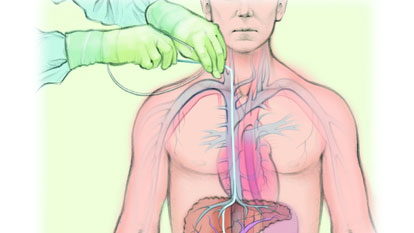

Transjugular Liver Biopsy

Transjugular Liver Biopsy (TJLB) is a minimally invasive procedure used to obtain liver tissue for diagnostic purposes...

TIPS (Transjugular Intrahepatic Porto-Systemic Stent Shunt)

Transjugular Intrahepatic Portosystemic Shunt (TIPS) is a minimally invasive procedure...